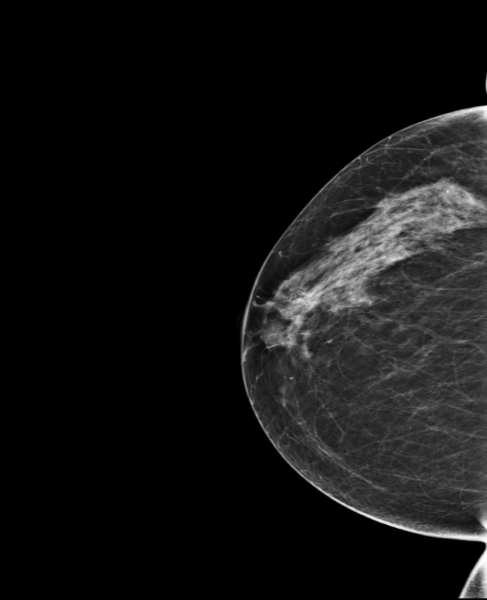

57 year-old woman, without risk factors, comes for a screening mammogram.

A 17mm mass (spicules included), not visible on the previous shot, is discovered in mammography, this mass is classified BI-RADS 5. MammoScreen® points this mass with a score of 8, as well as a second known benign mass. The mass measures 12 mm in ultrasound. The biopsy confirms CNST grade 1 Luminal A RO+ RP- HER2 low, Ki67 3%.